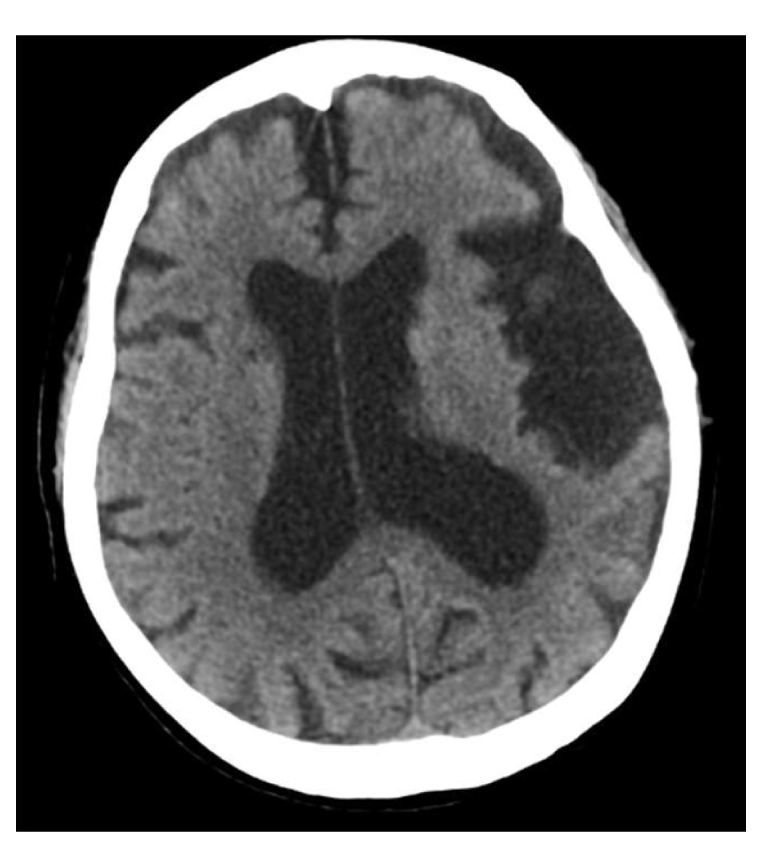

・頭部造影CT

脳梗塞・脳出血・脳腫瘍・脳動脈瘤・血管の狭窄・脳の萎縮などを調べます。